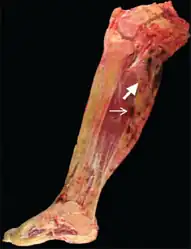

Per Nature, malignant Tenosynovial giant cell tumor tend to be "large, fleshy, and poorly circumscribed with areas of hemorrhage and necrosis" , while small histiocytes, larger mononuclear cells, siderophages were the given, histiologically.[11]